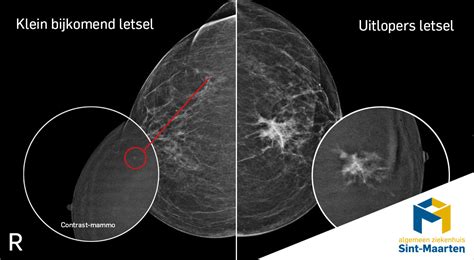

Voor vrouwen met zeer dicht borstklierweefsel is het bevolkingsonderzoek borstkanker extra belangrijk, hoewel tumoren hier minder goed op te sporen zijn. Er wordt onderzoek gedaan naar verbeterde screeningsmethoden, zoals contrast-mammografie (CEM) en verkorte MRI-onderzoeken (DENSE-2 studie), om borstkanker bij deze groep eerder op te sporen.

Het is niet mogelijk om van buitenaf te zien of te voelen hoe compact het borstweefsel is. Dit wordt pas duidelijk na een mammografie, de röntgenfoto die gemaakt wordt tijdens het bevolkingsonderzoek borstkanker. De radioloog classificeert de borstdichtheid in vier typen:

Ongeveer acht procent van de vrouwen die deelnemen aan het bevolkingsonderzoek borstkanker heeft zeer dicht borstweefsel (type D). Deze vrouwen hebben een tweemaal hogere kans op borstkanker dan vrouwen met een gemiddelde borstdichtheid. Dit komt doordat tumoren op een mammogram minder goed zichtbaar zijn in dicht klierweefsel, dat op de röntgenfoto wit is, net als een tumor. Vetweefsel is zwart en maakt tumoren beter zichtbaar.